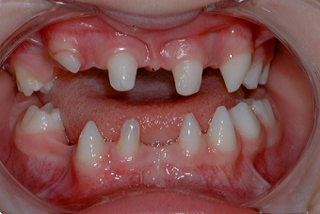

This case report is reviewed to best outline the management of a single oligodontia case. My orthodontic colleague and team member referred Jessica to my practice. She was 14 years old at the time of my initial examination.

Before my exam, the orthodontist treated and consolidated Jessica’s existing permanent teeth. He created tooth spaces for restoring missing permanent teeth and used fixed wires to maintain tooth position. The long-term treatment goal was to utilize implant-supported restorations when growth and development had finished.

Jessica’s primary concern was that “she wished she could change the appearance of her smile.” As discussed earlier, the esthetic effects of multiple missing teeth are a significant factor in these patients with oligodontia. Jessica was not comfortable with her tooth spaces and her small and worn retained primary lower teeth.

Although her prosthodontist had provided a “flipper” to replace the missing upper lateral incisors, she could not masticate or function well. She desired some “permanent” tooth replacements. She presented with no medical issues that would prevent dental restoration. Hers was a non-syndromic form of oligodontia. Her family (mother) did have a history of missing permanent teeth, but no one as severe as hers.

I applied the FGTP concepts taught in the Spear curriculum to establish tooth size and position. As you observe from the image provided, the remaining permanent teeth had tooth size discrepancies.

The microdontia that commonly occurs with oligodontia requires restoration of tooth size. The maxillary cuspids require increased contouring to improve esthetics and provide more normal-sized lateral incisors.

It is common with oligodontia to have retained primary teeth. Without the permanent tooth replacements, the primary tooth roots do not resorb at the expected rate. The templates provide opportunity to preview possibilities for tooth size and shape changes.